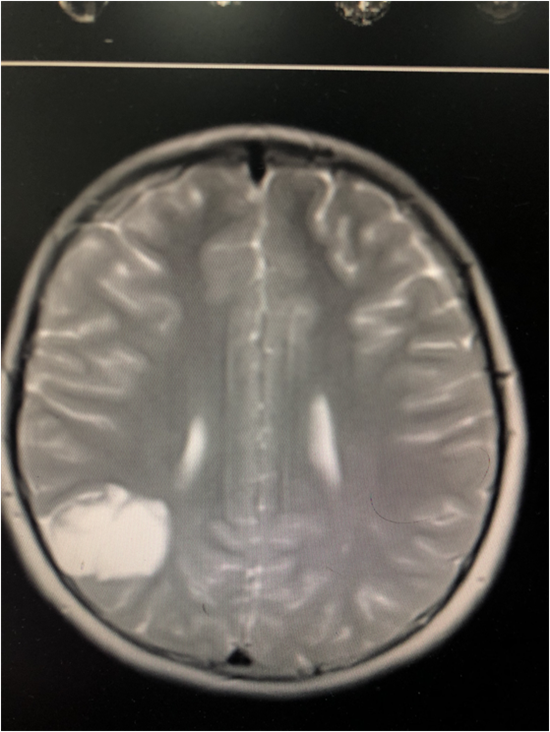

患儿陈某于7月22日因癫痫发作入住奉节县人民医院外二科,经检查发现患儿右顶叶生长了一个颅内肿瘤,肿瘤性质考虑低度恶性脑胶质瘤。对年仅11岁的孩子来说,无疑是残忍至极。这个巨大肿瘤就像一块巨型石头重重的压在女孩一家心上,懂事的女孩没有哭泣,然而家人却泪如雨下。

根据患儿情况,蒋永祥博士,杜洪澎教授及科主任丁晏和主管医师缪杰再三讨论,由于肿瘤位于重要功能区附近,术中稍有差池就有可能使患儿留下终身残疾,但是不充分切除肿瘤又会使肿瘤复发的机会增加。

做好精心准备及术中预案后,手术在麻醉科、超声科、重症医学科的支持与配合下顺利完全切除右顶叶脑胶质瘤切除术,术后患儿恢复良好,未遗留任何神经功能障碍,牵制着女孩命运的肿瘤终于被完整切下,女孩于8月8日出院。走的时候小女孩开心地说,她终于可以像其他正常女孩一样,做自己想做的事了。(作者:缪杰 编辑:王令军)